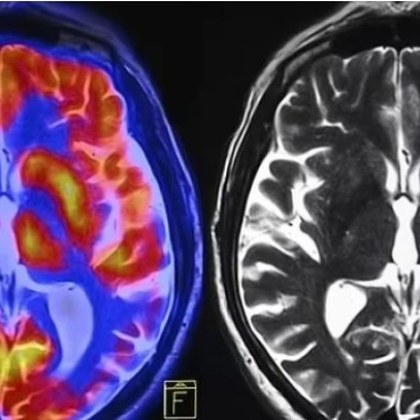

Учени се опитват да установят причините за различния начин по

...... процесите, които са специфични за даден пол и реакцията към терапевтични средства, ще подобри разработването на персонализирани лечения", допълва Линда Партридж, старши автор на изследването. /АКМ/ СПОДЕЛЕТЕ

Когато завършва образованието си през 1998 г д р Сабра Клейн

...... от научна гледна точка. В бъдеще обаче изводите ѝ могат да доведат до много промени – от начина на лечение до превенцията на различни болести.

Това е до голяма степен игнориран факт при жените лекарствата

...... от жените.Да, но отчитането на пола е скъпо начинание. Това може отчасти да обясни според изследовател защо разработването на ваксината, ефективна само при жени, в крайна сметка е било прекъснато.

Учени заявиха че продължителното въздействие на алкохола намалява електричната и

...... пиене? (ВИДЕО) По мнението на учените, трябва да се вземат под внимание половите различия при разработването на съвременни препарати за лечение на алкохолна зависимост.